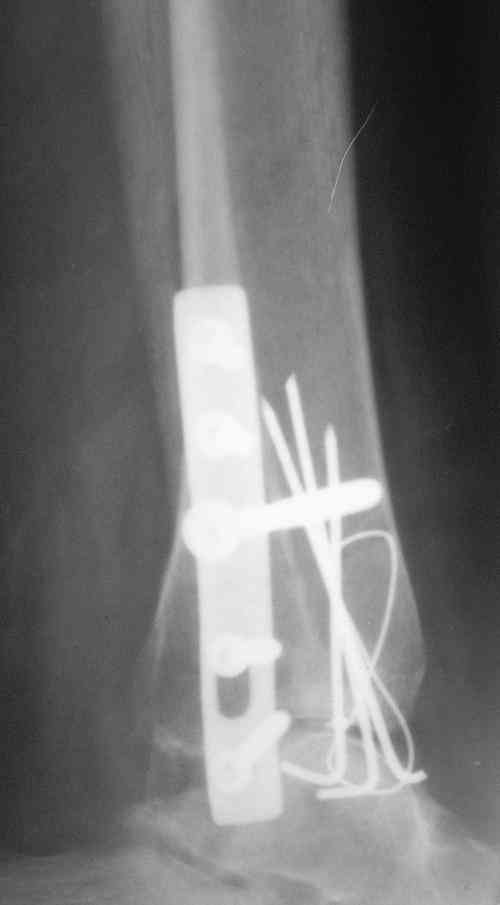

Завершая презентацию случая хотим показать результат операции. Прооперировали больную в соседнем отделении. На операции выраженый рубцовый процес в области синдесмоза, остеопоротические изменения в области медиальной и латеральной лодыжек. Провели удаление рубцовой ткани, остеосинтез медиальной и латеральной лодыжек с позиционным винтом на синдесмоз. Фото прилагаем. Благодарим за отзывы.